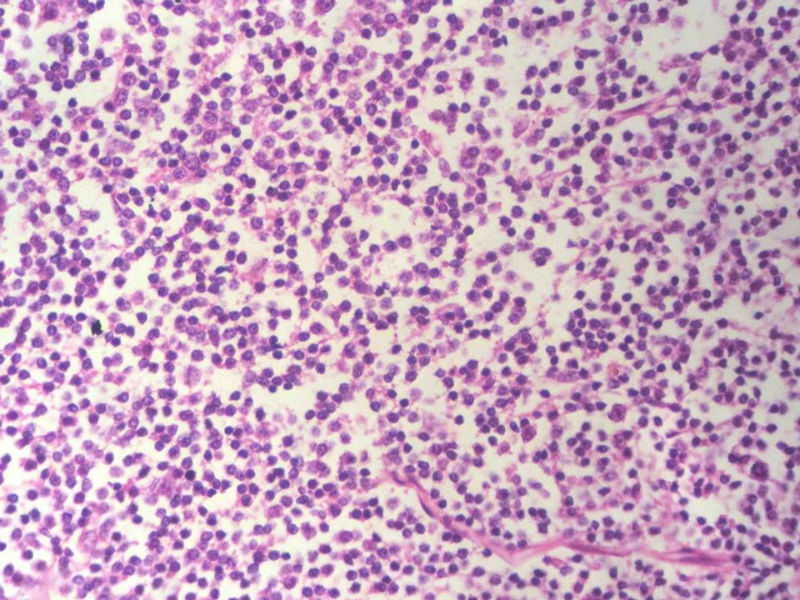

男,49岁,左眼睑球结膜下肿物2个月,手术切除。检查肿块3X2X2厘米,切面灰红色,质软。

本例是发生在特殊部位“结膜下”,HE肿瘤细胞形态形态一致,形似单核样B细胞。B细胞标记若明确阳性,诊断MALT是挺合理的。

HE:  1.MALT粘膜相关淋巴瘤:本例部位很特殊,位于“结膜下”,考虑MALT很合理;但本例镜下细胞形态很一致,诊断MALT是有难度的。

2. SLL小细胞淋巴瘤:就细胞形态而言,有相似之处,考虑SLL也有道理;但如果在没有发现淋巴结,肝,脾,骨髓或外周血具有病变的前题下,原发于结膜的SLL可能是少见的。

3.套细胞淋巴瘤:细胞大小及一致性比较符合;但本例核太规则了,套细胞淋巴瘤很难有这么规则的圆形或椭圆形。

4.滤泡性淋巴瘤: 可能性更小,暂时不考虑。

淋巴样细胞。细胞形态单一,细胞小。主要鉴别:

1)粘膜相关淋巴组织淋巴瘤

2)小细胞性淋巴瘤/慢性淋巴细胞性白血病

3)套细胞淋巴瘤

形态结构与细胞大小,似不支持滤泡性淋巴瘤。

淋巴瘤  细胞小  形态单一  主要考虑小B细胞淋巴瘤